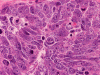

On permanent sections, there is extensive necrosis (Panel G) and there are numerous small islands of pyknotic or apototic nuclei (Panel H). In non-necrotic areas, the nuclei are large and pleomorphic. There are numerous mitotic figures (Panel I). Nuclear wrapping (Arrow in Panel J) is readily seen. The tumor is focally positive for synaptophysin, neurofilament proteins, glial fibrillary acidic protein, and diffusely positive for antibody BAF47.

Large cell (anaplastic) medulloblastoma is characterized by large, vesicular nuclei that are 5 times or more the size of a red blood cell. Marked variation in nuclear size and contour, and multinucleated, bizarre giant cells are other features. In particular, nuclear hugging or nuclear wrapping which refers one nucleus being surrounded by other nuclei as illustrated in this cases is a classic features of large cell medulloblastoma. In contrast to the classic type of medulloblastoma, the nucleoli are prominent, necrosis is prominent and extensive, extensive apoptotic or pyknotic cells are common. Large cell medulloblastomas have numerous mitotic figures that far exceed what would be expected in a classic medulloblastoma. Attempts has been made for a grading system of anaplstic changes in medulloblastoma 1 but the value of this system still has to stand the test of time 2, 3.